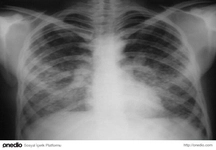

Temiz Akciğer Tomografisi Ne Anlama Geliyor?Günümüzde tıpta tanı ve tedavi süreçlerinde önemli bir yer tutan görüntüleme yöntemlerinden biri olan akciğer tomografisi, hastalıkların teşhisinde kritik bir rol oynamaktadır. "Temiz akciğer tomografisi" ifadesi, genellikle akciğerlerde herhangi bir anormal bulguya rastlanmadığı anlamına gelir. Bu bağlamda, temiz bir akciğer tomografisi sonucu, hastanın akciğer sağlığının iyi olduğunu gösterir. Akciğer Tomografisi Nedir?Akciğer tomografisi, yüksek çözünürlüklü görüntüler elde etmek için X-ray teknolojisini kullanan bir görüntüleme yöntemidir. Bu yöntem, akciğerlerin iç yapısının detaylı bir şekilde incelenmesine olanak tanır. Tomografi, akciğerlerdeki lezyonlar, tümörler, enfeksiyonlar ve diğer patolojilerin tespit edilmesinde son derece etkili bir yöntemdir. Temiz Akciğer Tomografisi SonucuTemiz bir akciğer tomografisi sonucu, şu durumları ifade edebilir:

Bu sonuç, genellikle hastanın akciğer sağlığının iyi olduğunu ve herhangi bir ciddi patoloji olmadığını gösterir. Ancak, bu sonuçlar her zaman kesin bir tanı anlamına gelmez; doktorun klinik değerlendirmesi ve hastanın genel sağlık durumu da göz önünde bulundurulmalıdır. Temiz Akciğer Tomografisinin ÖnemiTemiz akciğer tomografisi sonucu, özellikle kronik akciğer hastalığı, kanser riski veya enfeksiyon öyküsü bulunan hastalar için büyük bir rahatlık kaynağıdır. Bu durum, hastaların tedavi süreçlerine olumlu yönde katkı sağlar ve gereksiz endişeleri azaltır. Ayrıca, temiz bir tomografi sonucu, sağlık profesyonellerine hastanın durumu hakkında daha fazla bilgi verir ve gelecekteki muayene ve tedavi planlamalarına yardımcı olur. SonuçTemiz akciğer tomografisi, akciğer sağlığının iyi olduğunu gösteren önemli bir bulgudur. Ancak, bu sonucun değerlendirilmesi için mutlaka bir sağlık profesyoneliyle görüşülmesi gerektiği unutulmamalıdır. Her durumda, kişinin genel sağlık durumu, belirtiler ve diğer tetkiklerin sonuçları birlikte ele alınmalıdır. Sağlıklı bir yaşam tarzı, düzenli kontroller ve zamanında yapılan tetkikler, akciğer sağlığının korunmasında önemli rol oynamaktadır. |